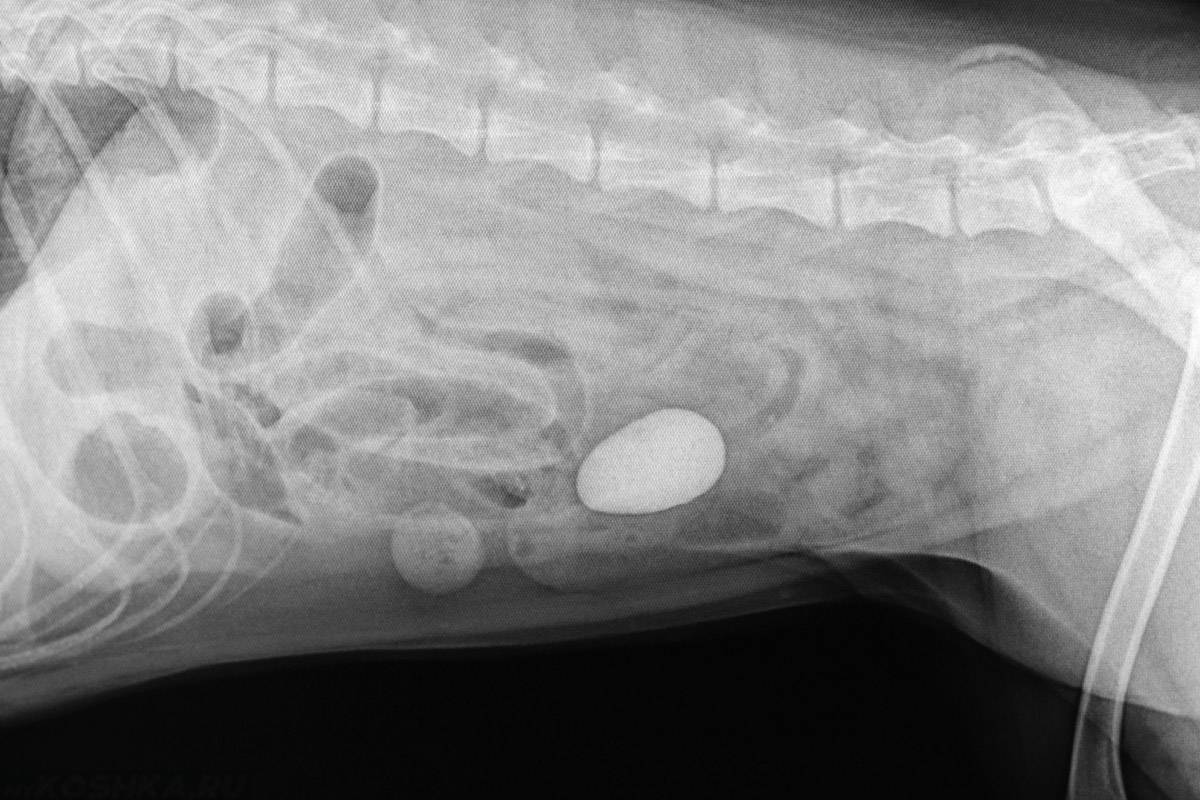

Непроходимость кишечника у собаки из-за камня

- Кишечная непроходимость. Если был проглочен камень крупных размеров, то он может закупорить кишечник. В этом случае спасет питомца только быстро сделанная операция.

- Кишечной непроходимости . К сожалению, при данной патологии часто животные гибнут, так как проглоченные предметы, в том числе, камушки, приводят к закупорке кишечника, но только в том случае, если питомцу не оказывается своевременная медицинская помощь. При кишечной непроходимости требуется хирургическое вмешательство. Острое заболевание развивается внезапно, стремительно, сопровождается выраженной симптоматикой – рвотой, слабостью, вялостью, вздутием живота, болезненностью. Пес чаще лежит, не интересуется окружающим, в том числе, содержимым собственной миски.

Камни в пищеводе создают непроходимость кишечника. Без экстренной хирургической помощи велик риск летального исхода. Распознать проблему можно по внешним признакам (потеря аппетита, повышение температуры тела, проявления интоксикации), но диагноз поставит только опытный ветеринар.

- Кишечной непроходимостью. Проглоченный камень может закупорить кишечник, стать причиной непроходимости. Отсутствие хирургического вмешательства чревато летальным исходом.